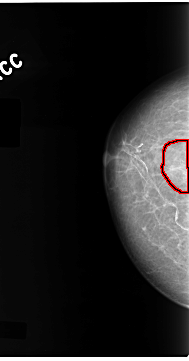

C_0099_1.RIGHT_CC

RIGHT_CC LINES 4688 PIXELS_PER_LINE 2456 BITS_PER_PIXEL 12 RESOLUTION 50 OVERLAY

FILE: C_0099_1.RIGHT_CC.OVERLAY

TOTAL_ABNORMALITIES 1

ABNORMALITY 1

LESION_TYPE CALCIFICATION TYPE PLEOMORPHIC DISTRIBUTION CLUSTERED

ASSESSMENT 5

SUBTLETY 5

PATHOLOGY MALIGNANT

TOTAL_OUTLINES 1

BOUNDARY